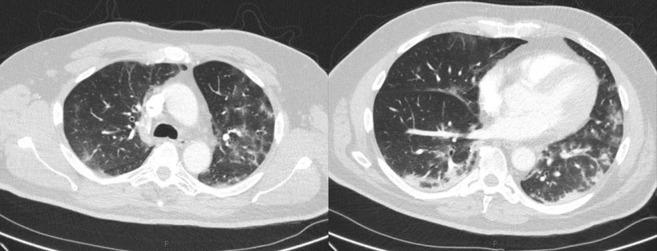

A 49-year-old man was admitted to his local hospital with left leg pain and breathing difficulties. He had negative nasopharyngeal polymerase chain reaction tests for severe acute respiratory syndrome coronavirus 2. Chest X-ray and Computed tomography pulmonary angiogram displayed typical coronavirus disease 2019 (COVID-19) radiological features as ground-glass opacities and bronchovascular thickening. His respiratory symptoms resolved after four days of supportive treatment, whereas his left leg became more painful and discolored. He was referred to our center with acute left leg ischemia. computed tomography angiogram revealed eccentric mural thrombus at the aortic bifurcation, extending into left common iliac and an abrupt occlusion of left popliteal, tibioperoneal, and posterior tibial arteries. He was treated with catheter-directed thrombolysis for 48-hours that achieved successful revascularization of the ischemic limb with no intervention-related complications. At six-week follow-up, he showed full recovery. Our case demonstrates that catheter-directed thrombolysis is a successful and safe treatment option in a COVID-19 patient with acute arterial occlusion.

一位 49 岁男性因左腿疼痛和呼吸困难入住当地医院。他的鼻咽聚合酶链反应检测严重急性呼吸综合征冠状病毒 2 呈阴性。胸部 X 光和计算机断层肺动脉造影显示出典型的 2019 年冠状病毒病(COVID-19)放射学特征,包括磨玻璃影和支气管血管增厚。经过四天的支持性治疗,他的呼吸症状得到缓解,但左腿变得更加疼痛和变色。他因急性左腿缺血被转至我们中心。计算机断层血管造影显示主动脉分叉处偏心性壁血栓形成,延伸至左侧髂总动脉,以及左侧腘动脉、胫前动脉和后胫动脉突然闭塞。他接受了 48 小时的导管定向溶栓治疗,实现了缺血肢体的成功再血管化,没有与干预相关的并发症。在 6 周的随访中,他完全康复。我们的病例表明,在 COVID-19 患者中,导管定向溶栓是一种成功且安全的治疗选择。